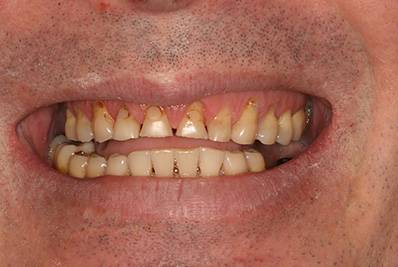

6. Eset

Nagymértékű fogkopás, erózió, csikorgatás a teljes rágóapparátust túlterhelve okoz reménytelennek tűnő helyzeteket.

Ebben az esetben implantátumok , koronák és hidak segítségével változtattunk a páciens fogainak érintkezésén. 6 hónapig ideiglenes hidakkal teszteltük a megváltoztatott harapási pozíciót. Ezután készültek el a végleges fix pótlások.